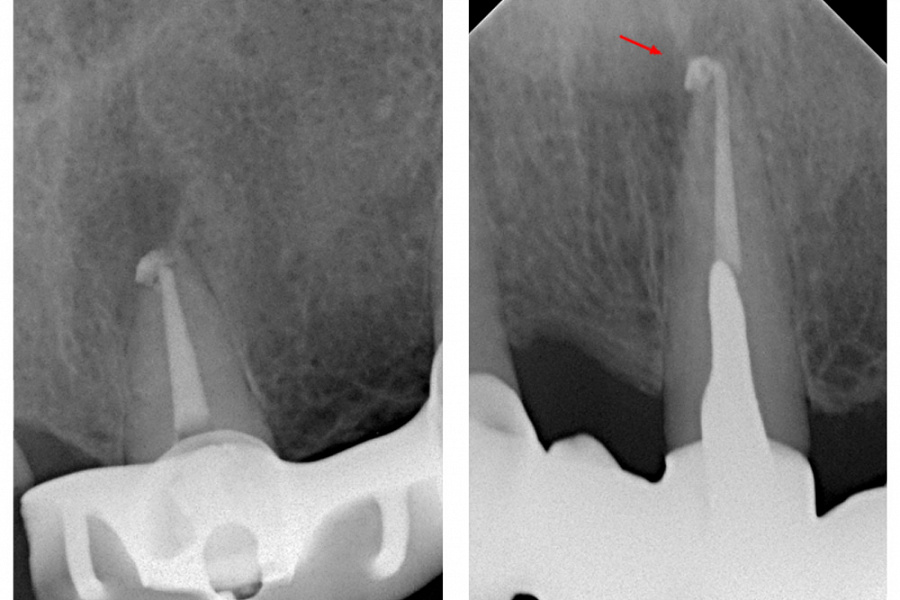

В связи с наличием у пациента жалоб и клинических симптомов принято решение о проведении ревизии корневого канала 21 зуба. Проведена терапия с помощью гидроокиси кальция в течении 4-х недель (снимок 3). Пломбировка канала гуттаперчей и корневым герметиком.